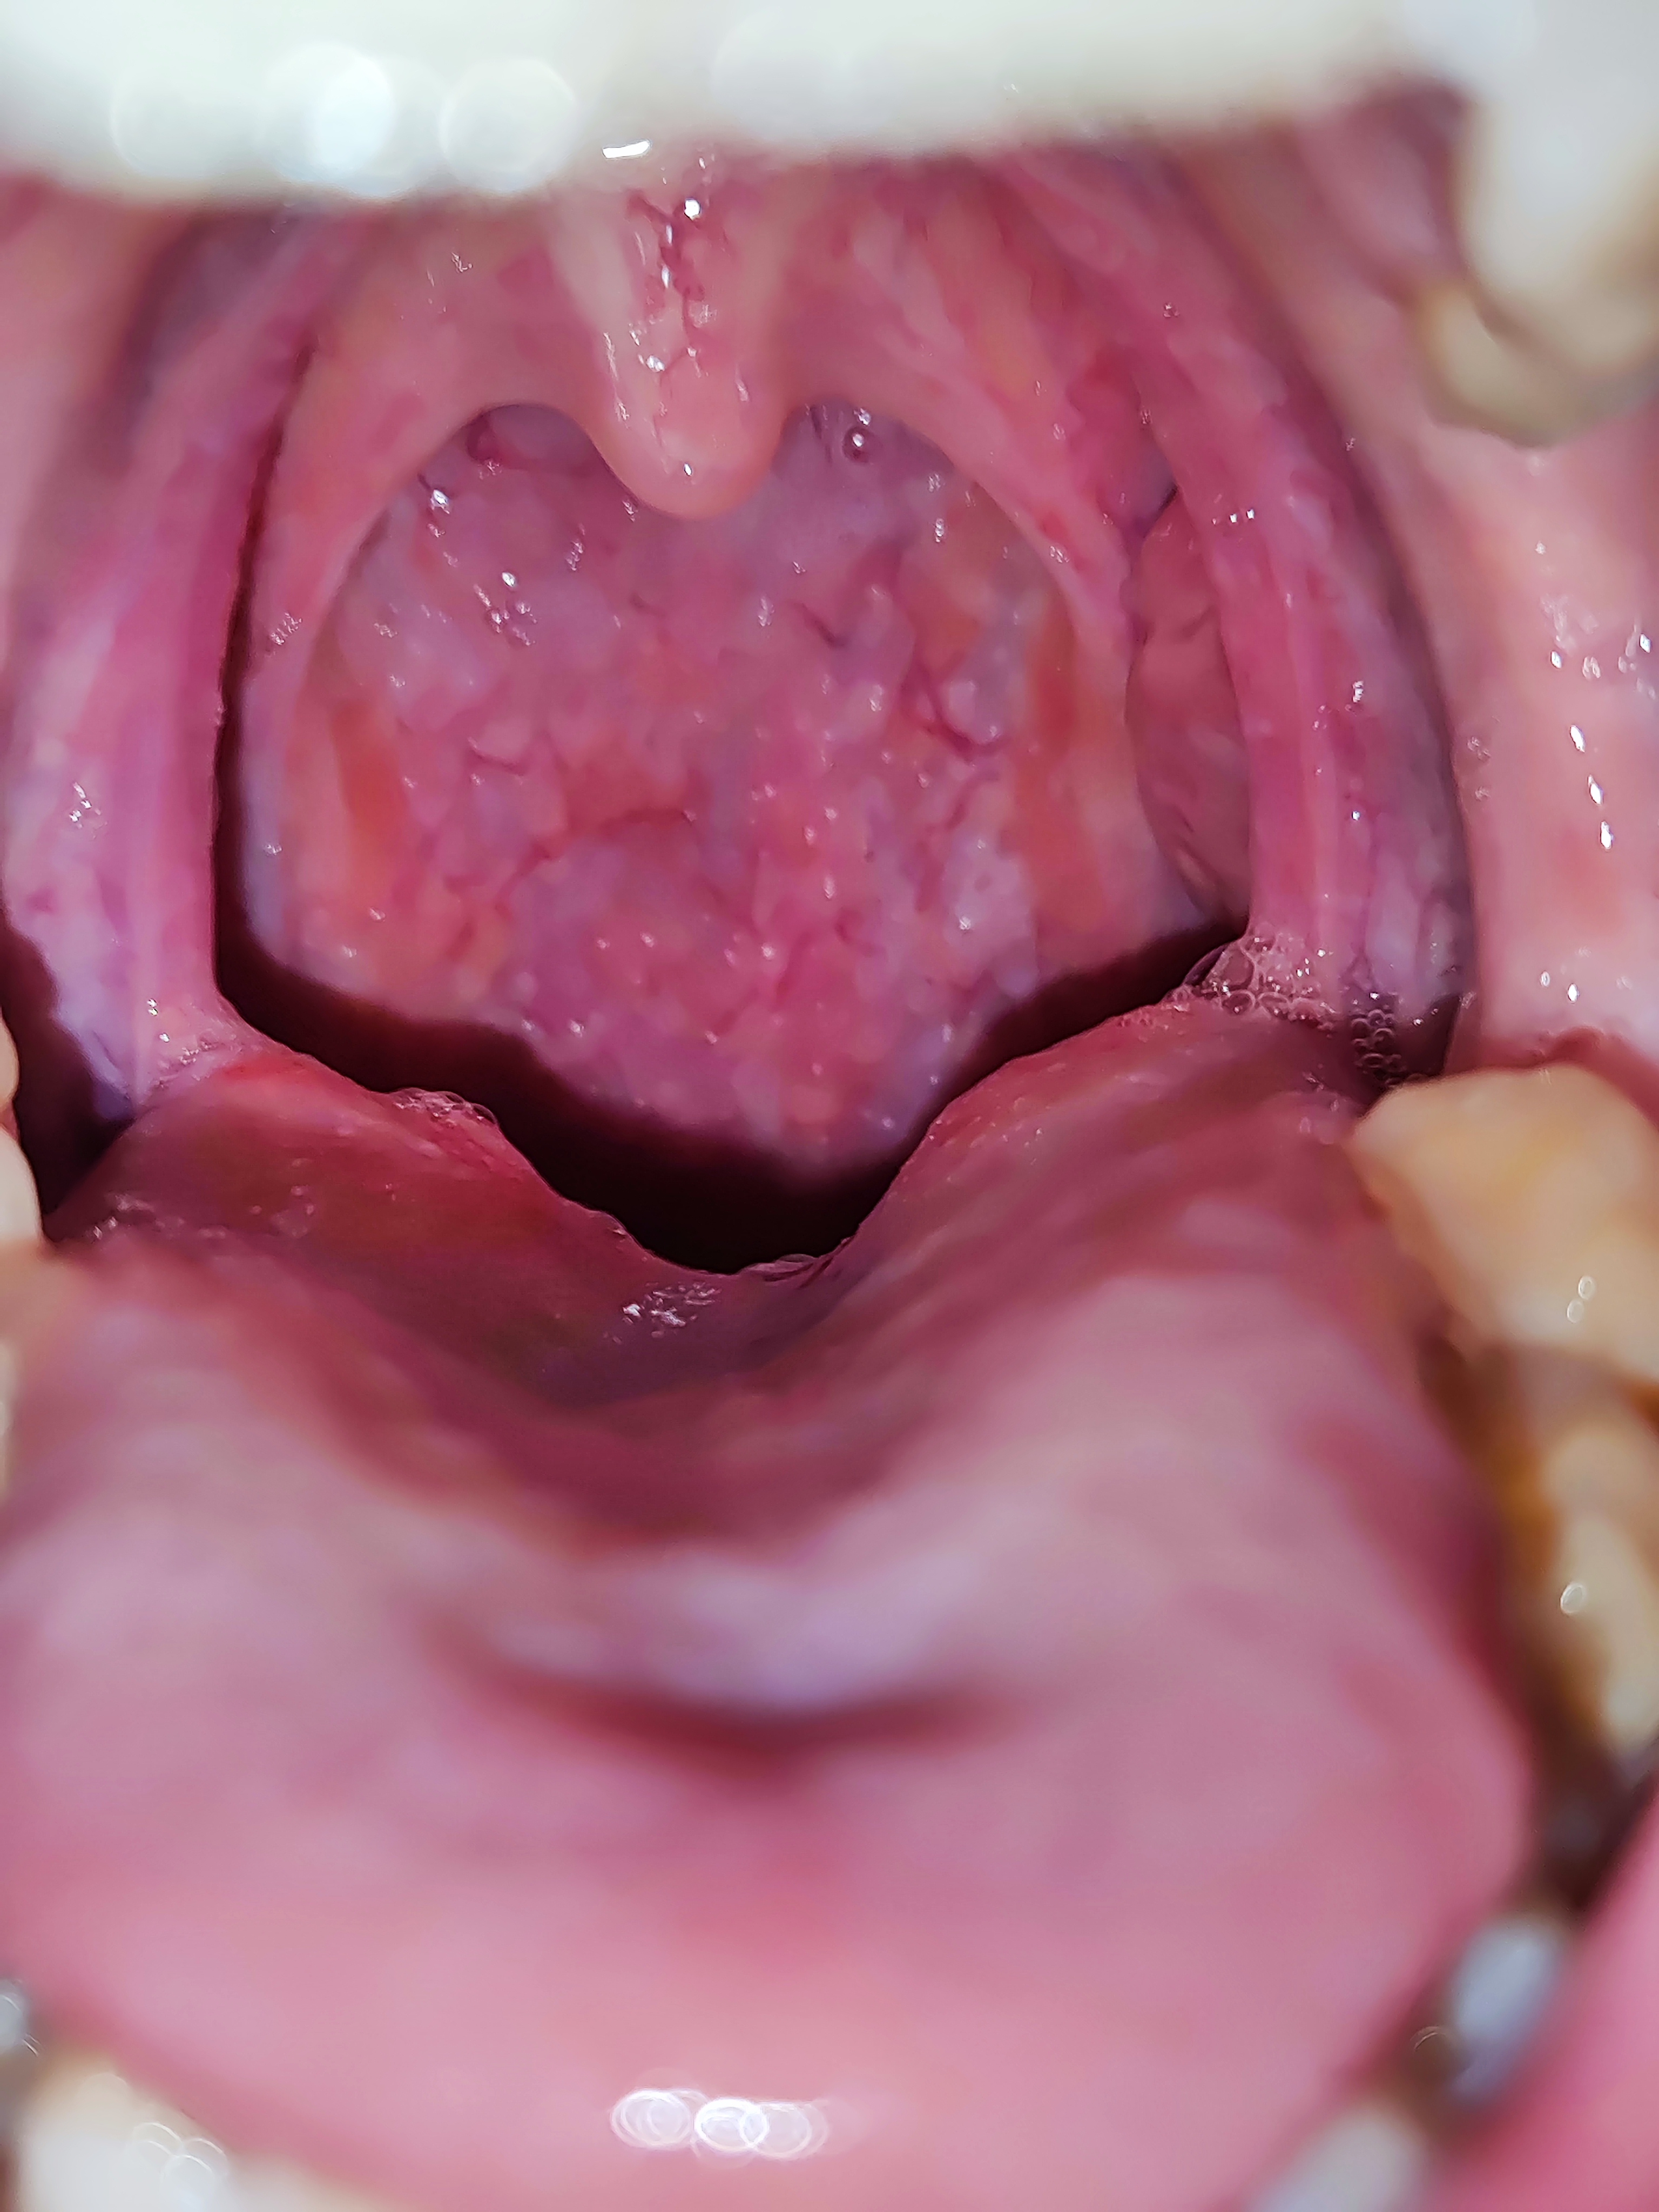

Фарингита -тред. Горло красное всегда, глаза побаливают, отëчность, под челюстью узлы немного непр